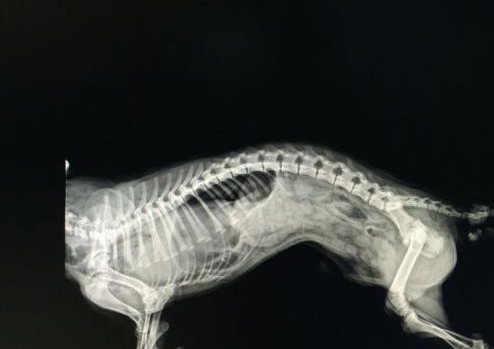

每年在10000例出生婴儿中(包括活产和死产)中约有2.5~3.8例患有该疾病。尽管现代科学技术的进步使CDH 诊治水平已取得很大进展, 包括应用不同的辅助通气法、吸入一氧化氮疗法、使用外源性肺泡表面活性物质等药物、体外膜肺式氧合器(ECOM) 、外科技术的改进( 腹腔镜的使用) 等, 但目前CDH 患儿的死亡率仍为30% ~ 60% 。其病死率高的主要原因在于患儿常合并不同程度肺发育不良 。先天性膈疝缺乏构成膈疝先天性膈疝可分3 种类型:第1 型为后外侧疝, 亦称胸腹裂孔疝;第2 型为胸骨旁疝;第3 型为食管裂孔疝。